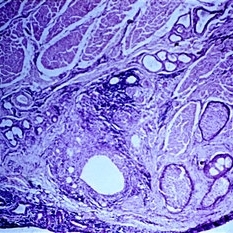

Slide 5-36 Slide 5-36Feb 25 2019 by Lancaster Course in Ophthalmology Basal cell carcinoma originating from five separate sites in the surface epithelium over the lacrimal punctum and canaliculus. Condition/keywords: basal cell, canaliculus, epithelium, lacrimal punctum

Slide 5-37 Slide 5-37Feb 25 2019 by Lancaster Course in Ophthalmology Edge of squamous cell carcinoma of the skin showing sudden change from normal epithelium to infiltrating islands of large, malignant squamous cells. Condition/keywords: epithelium, squamous cells